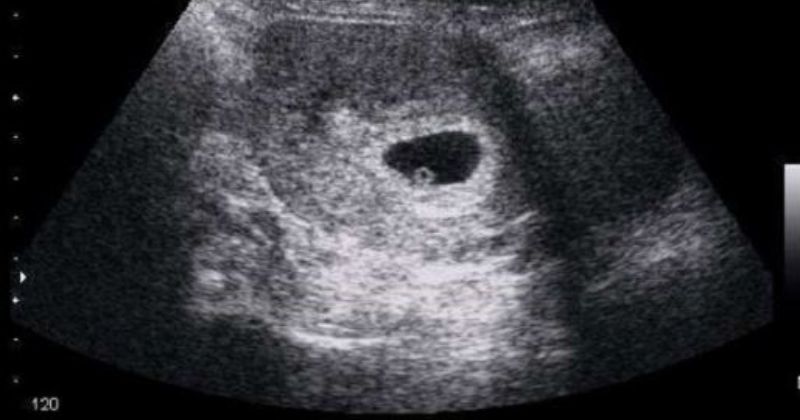

Mang thai 2 tuần siêu âm có thấy không?

Siêu âm là phương pháp chính xác và tối ưu nhất để các mẹ xác định liệu mình có mang thai hay không. Tuy nhiên khi các mẹ mang thai 2 tuần thì vẫn nằm trong thời gian rụng trứng nên chưa chắc chắn trứng đã được thụ thai hoặc trứng đã được thụ tinh nhưng chưa làm tổ ở tử cung. Vì thế, siêu âm trong giai đoạn này kết quả sẽ không chính xác. Thời điểm để các mẹ siêu âm tốt nhất là từ 7 -10 tuần sau khi có dấu hiệu mang thai.